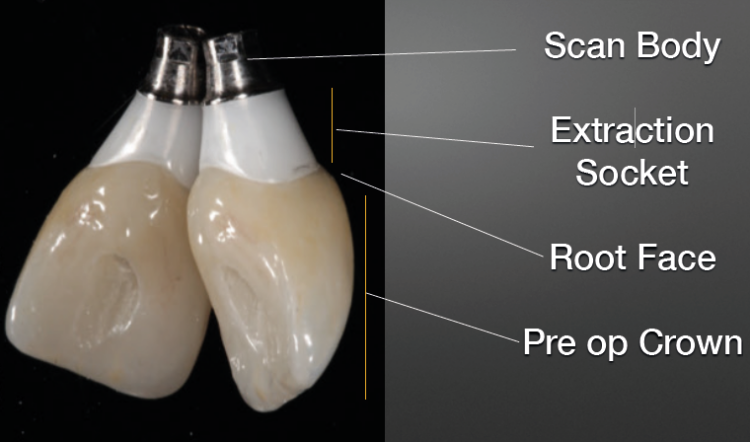

Firstly, a scan was taken of the preoperative situation, so the team had a clear picture of the starting point. Next, the crown was severed from the tooth, leaving the root. Another scan was taken to gather all the information needed in relation to what the tooth looked like at gum level, so the restoration (crown) could be created to support the gum at the necessary level in the same way.

The root was then removed, and a scan of the soft tissue taken to record the internal surface of the gum at that height, which drives the shape of the subgingival portion of the crown. Implant placement took place alongside the introduction of bone grafting material (Bio-Oss Collagen), to push out the gingiva and form as bone in the desired shape.

A final scan was taken, with an iSy titanium base connected to the abutment, so that the Cerec machine had all the data it needed about the exact location of the implant, its orientation, etc.

The crown could then be created that would fit on to the implant, using the software. The shape of the subgingival portion of that crown was to support the subgingival tissue in the same way – and at the correct level – that the natural tooth had prior to extraction.